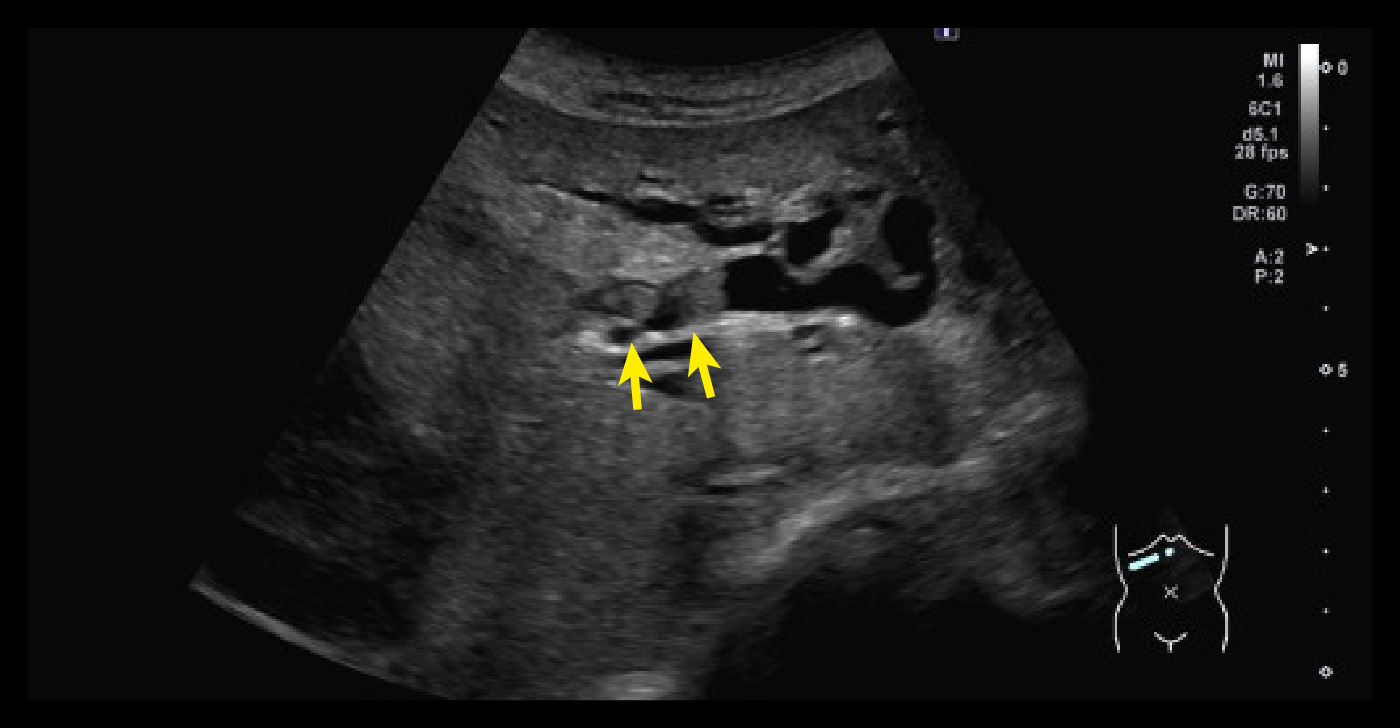

エコー 胆嚢底部を主座とした不整形腫瘤/腫瘤内血流シグナル

左から エコー 胆嚢底部を主座とした不整形腫瘤/腫瘤内血流シグナル